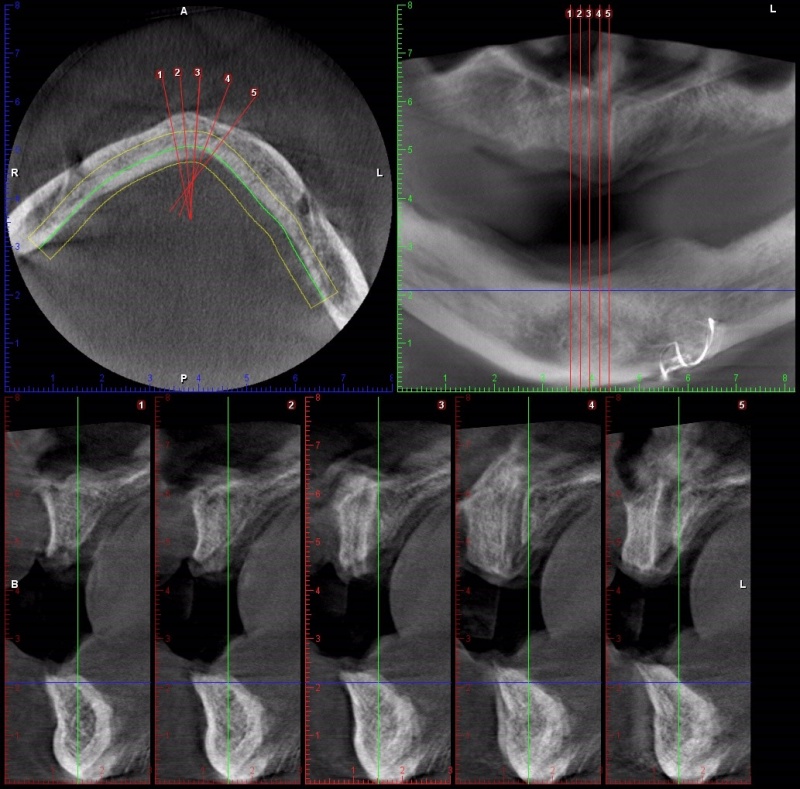

- Radiographs for Implants

- Guided Implant Placement

- Steps in Making a Surgical Guide